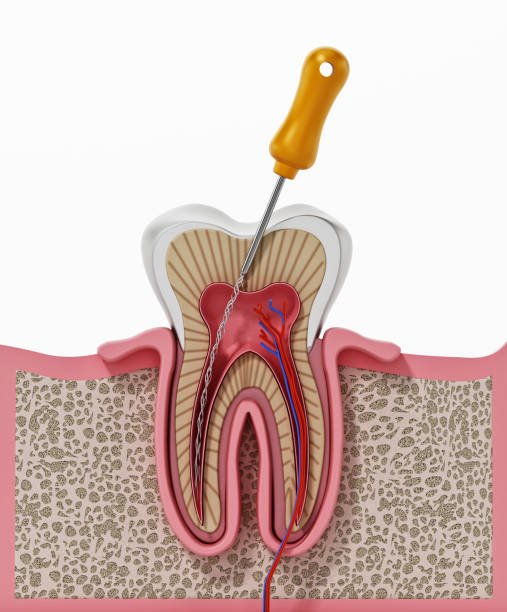

Dr. Jinu George Byju is the chief endodontist at Alex Dental Studio. He completed his BDS from MES Dental College, Perinthalmanna, and pursued MDS in Conservative Dentistry and Endodontics from Yenepoya Dental College, Mangalore. With advanced training in pediatric dentistry, minor surgical procedures, and orthodontics, Dr. Jinu combines precision with compassion to provide high-quality, patient-centered care.